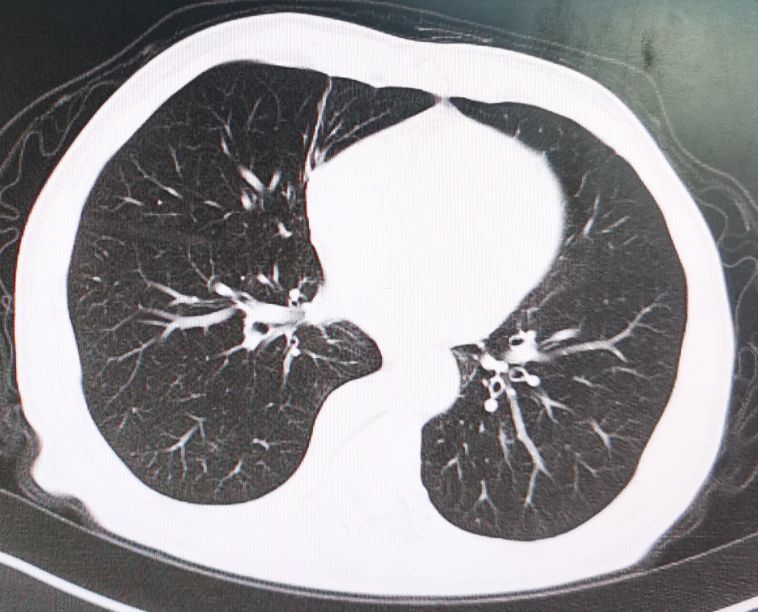

经联合化疗及靶向药物治疗六个周期后,病人双肺的转移病灶完全消失,随后进行维持治疗至今没有发现新的转移病灶。

6个周期化疗及靶向药物治疗后转移病灶完全消失